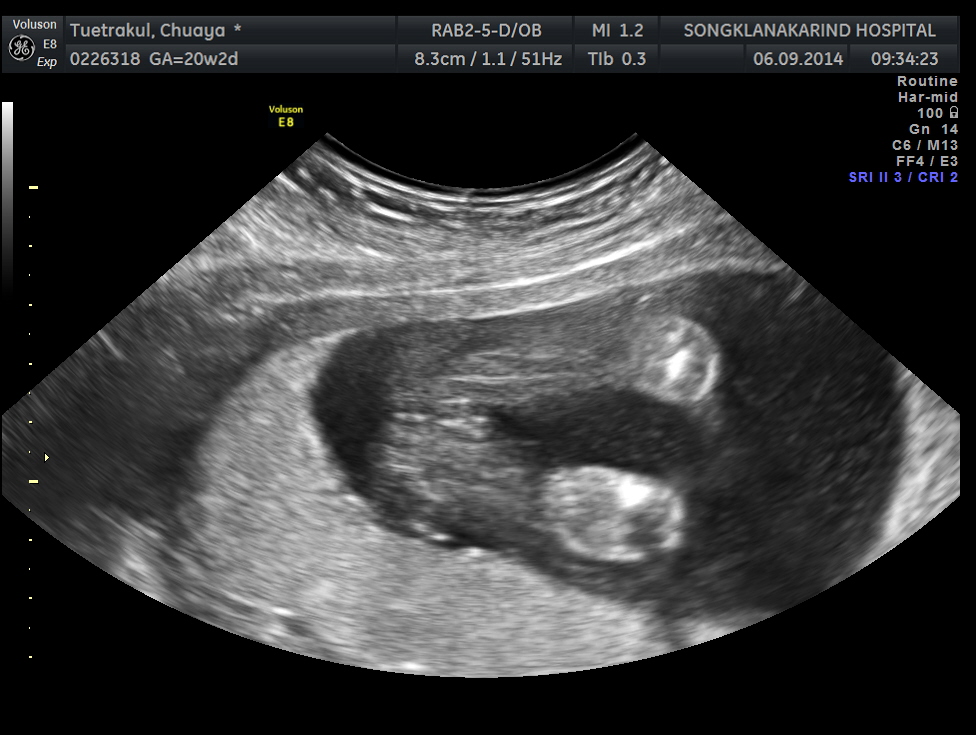

ช่วยดูให้หน่อยได้ไหมคะ ว่าภาพอัลตร้าซาวด์ เป็น ผู้หญิง หรือ ผู้ชาย คะ?

ไปซาวด์ตอนอายุครรภ์ได้ 20 สัปดาห์ หมอบอกว่า ผู้หญิง ค่ะ

แต่พอท้องโตได้ 28 สัปดาห์ หมอคัดท้อง 2 คน และ ญาติๆ ต่างพากันทักว่า ว่าเป็นผู้ชายรึเปล่า? เพราะลักษณะท้องบ้าง สะดือบ้าง ออกแนวผู้ชาย

ก็เลยเอาผลอัลตร้าซาวด์มาดูอีกรอบ แต่ก็ยังไม่แน่ใจ เพราะดูไม่เป็นค่ะ

ขอรบกวนช่วยดูให้หน่อยนะคะว่าเป็นเพศชาย หรือ หญิงกันแน่ค่ะ